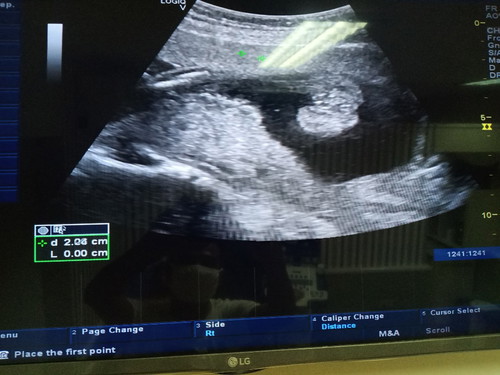

เพศลูก

พึ่งไปซาวมาคะ แม่ๆดูเป็น หญิงหรือชายคะ หมบอกผญ.คะ เห็นกลีบ แต่ยังไม่ชัวร์คะ

20Weekค่ะ

ตรงนั้นเป็นหว่างขาน้องไหมคะแม่ ถ้าใช่น่าจะผช.นะคะ

ตรงนั้น เป็นหว่างขากับก้นน้องคะ

เป็นหว่างขากับก้นน้องคะ